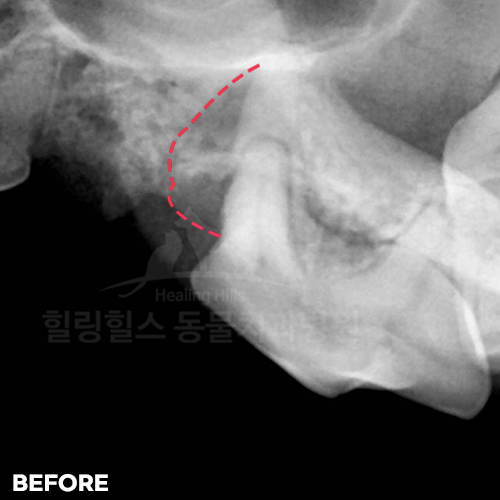

양도가니 먹고 부러진 강아지어금니! 발치하지 않고 자기치아살리는 힐링힐스 동물치과병원

2025.08.13